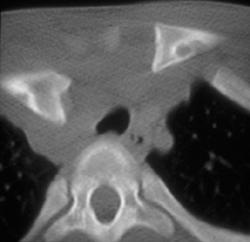

Neurofibroma (right Side)